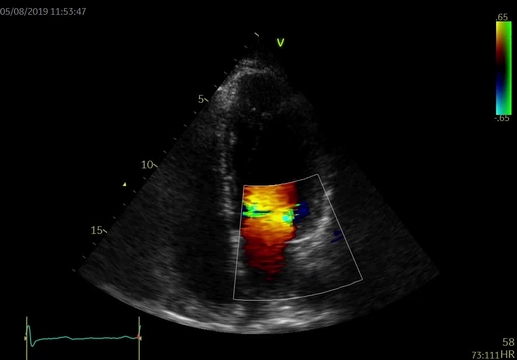

Koronarografické vyšetření provedené cestou stacionáře prokázalo hemodynamicky nevýznamné stenózy koronárních tepen – 30% stenózu RIA II a 50% stenózu odstupu RD1 (video 3). Pro nález koronární aterosklerózy byla do terapie přidána kyselina acetylsalicylová 100 mg/d.

Video 3. Selektivní koronarografie. 3A – zobrazení levé koronární tepny, 3B – zobrazení pravé koronární tepny. Nález bez hemodynamicky významných stenóz